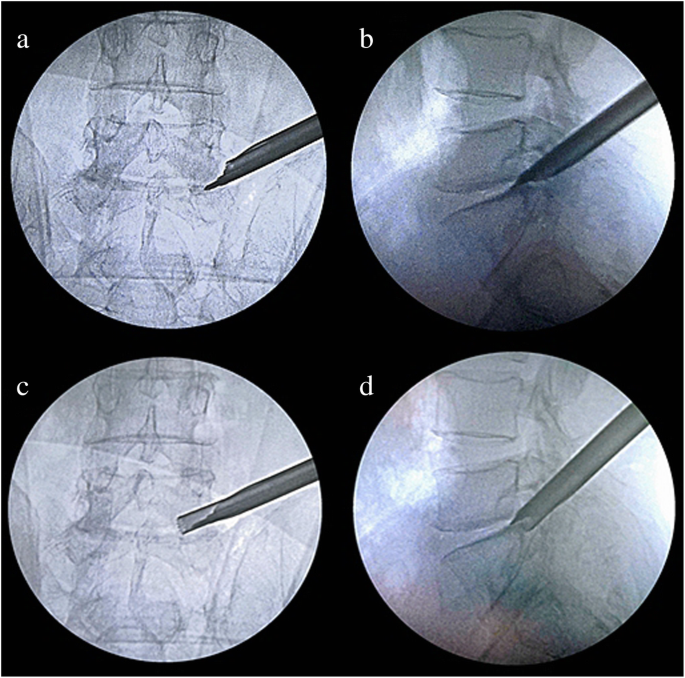

The targeted and quantificational foraminoplasty process: a, b Following Kirschner wire insertion, the double-cannula device with a properly predetermined diameter was inserted and rotated for a predetermined trajectory. c, d Foraminoplasty was performed by a trephine; the exiting nerve root was excluded from the working zone and the Kirschner wire acted as a steady pivot

Secondly, the ZESSYS device can improve the efficiency and safety of foraminoplasty. As mentioned above, among the anatomical limitations at the L5–S1 level, the iliac crest is considered a major obstacle [25, 26]. When the iliac crest is located above the middle of the L5 pedicle in the lateral radiograph, foraminoplasty may be required [27]. In addition, if the working spaces are limited by the other anatomical limitations, foraminoplasty is also necessary. In the conventional TESSYS technique, the foramen is widened gradually by an isocentric trephine. During the process of foraminoplasty, the trephine blade makes close contact with foramen soft tissue and nerve roots, leading to a risk of damage, especially for the L5–S1 level with a narrowed disc space and intervertebral foramen than the other levels. During the PTED process with ZESSYS, a 2.5-mm Kirschner wire is passed between the SAP and exiting nerve root and fixed on the posterior aspect of the distal vertebra, which acts as a steady pivot for the double-cannula device. When the predefined cannula is inserted to dock on the SAP at posterior orientation, it can be easily rotated to find the proper trajectory and achieve quantificationally decompression. In addition, the beveled design cannula is placed next to the ventral side of the SAP, excluding the exiting nerve root from the working zone of the trephine and protecting the exiting nerve root from damage. If needed, the foramen can be enlarged by a second cannula rotation. The double cannulas greatly reduce the difficulty of foraminoplasty and enable foraminoplasty to be performed more precisely (Figs. 3 and 4).